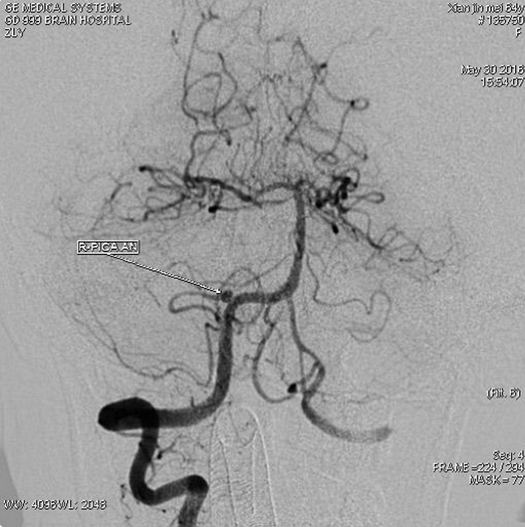

右椎动脉造影:右侧小脑后下动脉瘤,大小约2.7×3.0mm;瘤颈口与右侧小脑后下动脉开口关系密切